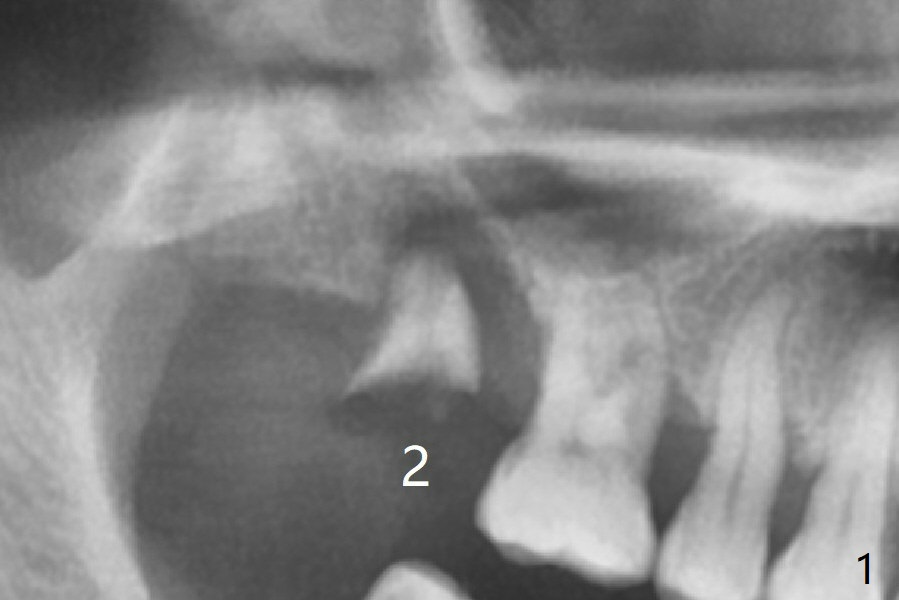

After extraction of the tooth #2 (Fig.1), osteotomy is supposed to be initiated in the mesial slope (Fig.2 arrow). With Magic Expanders (3-4.8 mm), osteotomy ends up in the bottom of the socket (Fig.3). Trajectory is found to be off when 4x9 and 5x9 mm dummy FC implants are placed with stability (Fig.4,5). The final implant, Magicore (5x7(3)mm, >29 Ncm), appears to be placed too deep for restoration (Fig.6,7); a screw retained crown may be a solution. PRF membrane and Vanilla (allograft) are used for sinus lift (no sinus membrane perforation). Following Vanilla graft in the socket gap (Fig.6 *), another piece of PRF membrane is used to cover socket opening. The membrane is fixed in place with suture and periodontal dressing. The implant seems to have osteointegrated 3.5 months postop (Fig.8). After change to 4.3x5 mm solid abutment and mesial surface adjustment, impression is taken for early loading because of removal of #14 implant. In fact the patient is satisfied with mastication improvement at #2 later on.